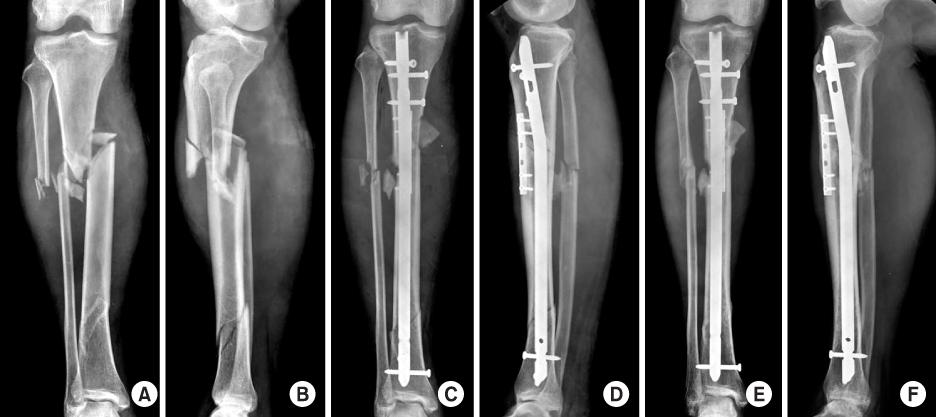

Fig. 9

(A, B) Initial radiographs show the segmental fracture of the proximal and distal tibial shafts.

(C, D) The proximal fracture was reduced and stabilized with a 1/3 tubular plate through a small incision before locked tibial nailing to prevent malalignment. Postoperative radiographs show anatomical alignment of the fracture fixed with a locked nail and a small plate.

(E, F) Radiographs 7 months after surgery show the healed fracture with external callus in good alignment.